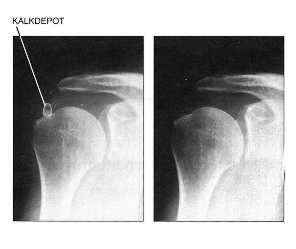

Left: Before the operation, there was a large calcium deposit in the tendon cap.

Right: State after arthroscopic decalcification.